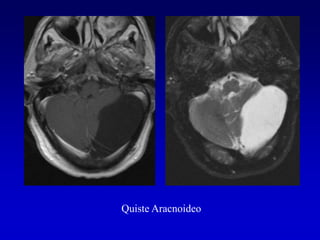

3 QUISTE ARACNOIDAL

Quiste Aracnoideo

DWIFLAIR